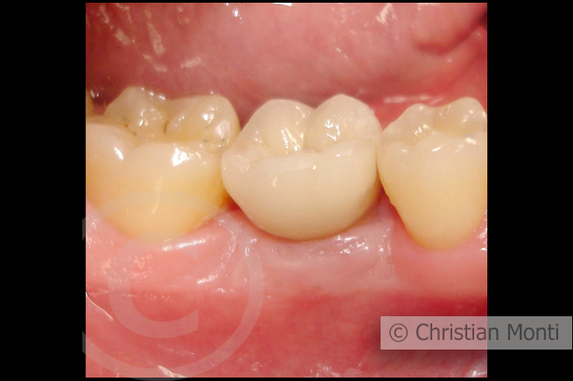

EDENTULIA SINGOLA

Impianto dilazionato in sostituzione di un molare inferiore